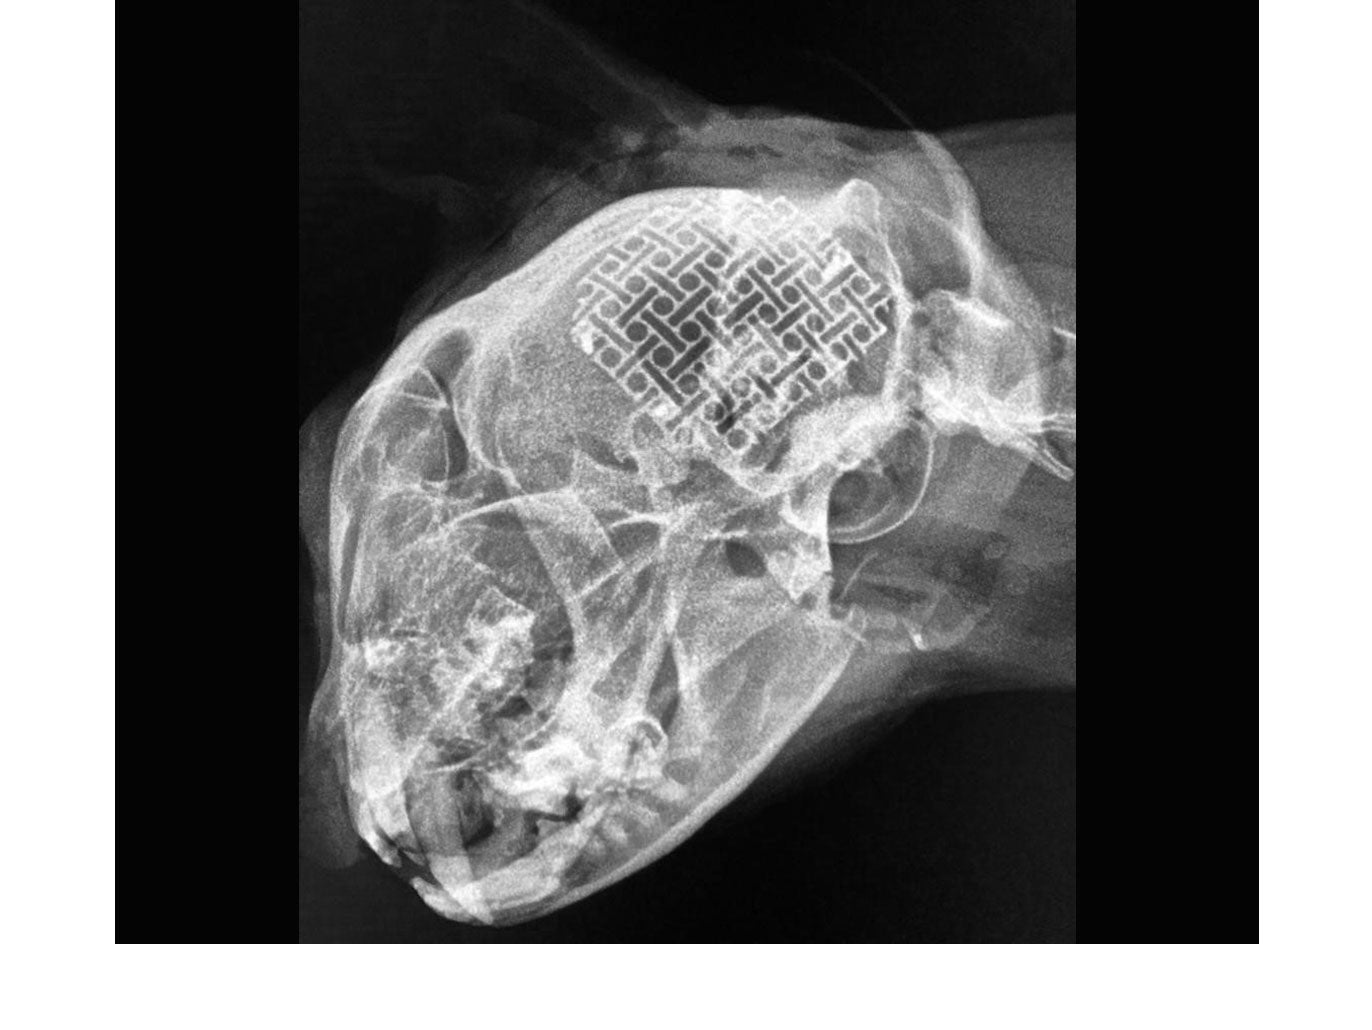

neuromesh™ is a cuttable, medical grade titanium cranioplasty solution which can be moulded to match the skull shape of each individual patient, regardless of their size.

neuromesh™ provides for the ability of "on site" engineering, allowing the surgeon more versatility when faced with repairing skull defects or maxillofacial reconstruction. It can be used to maintain the aesthetic appearance of the patient, provide for structural support and protect the brain when surgery requires the removal of excessive amounts of skull. It saves time and opens the door to more advanced cranioplasty procedures.

Cuttable and easy to contour makes neuromesh™ a perfect solution for the reconstruction of cranial defects. Easily adaptable to contour to the anatomical curvature of craniums all varying shapes and sizes and uses low-profile titanium screws for fixation.